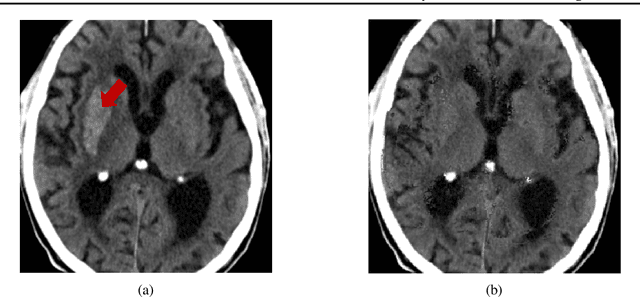

Segmentation masks of pathological areas are useful in many medical applications, such as brain tumour and stroke management. Moreover, healthy counterfactuals of diseased images can be used to enhance radiologists' training files and to improve the interpretability of segmentation models. In this work, we present a weakly supervised method to generate a healthy version of a diseased image and then use it to obtain a pixel-wise anomaly map. To do so, we start by considering a saliency map that approximately covers the pathological areas, obtained with ACAT. Then, we propose a technique that allows to perform targeted modifications to these regions, while preserving the rest of the image. In particular, we employ a diffusion model trained on healthy samples and combine Denoising Diffusion Probabilistic Model (DDPM) and Denoising Diffusion Implicit Model (DDIM) at each step of the sampling process. DDPM is used to modify the areas affected by a lesion within the saliency map, while DDIM guarantees reconstruction of the normal anatomy outside of it. The two parts are also fused at each timestep, to guarantee the generation of a sample with a coherent appearance and a seamless transition between edited and unedited parts. We verify that when our method is applied to healthy samples, the input images are reconstructed without significant modifications. We compare our approach with alternative weakly supervised methods on IST-3 for stroke lesion segmentation and on BraTS2021 for brain tumour segmentation, where we improve the DICE score of the best competing method from $0.6534$ to $0.7056$.